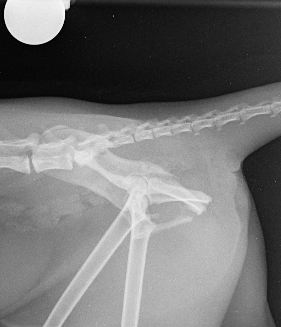

On presentation, she was unable to bear weight on her pelvic limbs. Withdrawal reflex and nociception were present, with normal proprioception in the right pelvic limb but delayed in the left. X-rays confirmed a right sacroiliac luxation, a left oblique ilium body fracture, a left ischium fracture involving the acetabulum, and bilateral pubic fractures (Figs. 1 and 2).

Fig. 1